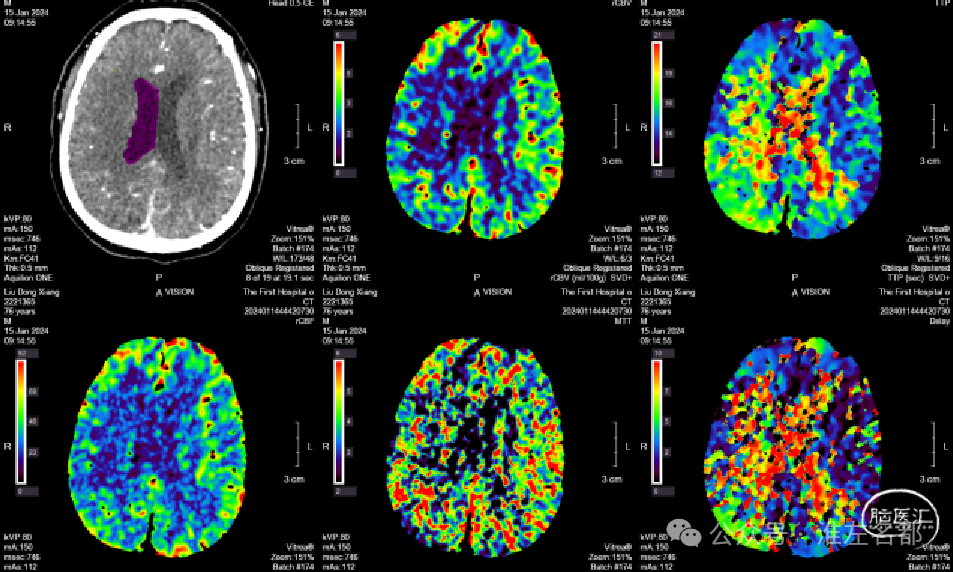

2024-01-14 08:36

复查多模式CT

CT平扫:双侧胼体膝部和右侧额顶叶皮质多发梗死低密度影。

CTA:右侧大脑前动脉原A2段狭窄位置管腔闭塞。

脑CTP:右侧大脑前动脉供血区较大范围TTP显著延长。

其次,由于已知患者此次发病由颅内动脉粥样硬化狭窄所致,当到院后24小时内症状明显加重时,故考虑可能是右侧A2狭窄闭塞所致,再次多模式CT表明原右侧A2狭窄处确实闭塞了,伴其供血区明显低灌注,但核心梗死不明显。右侧A2闭塞考虑原因是狭窄处急性血栓形成。此时,综合病情和多模式CT结果的动态变化情况,为阻止病情进展,挽救危险低灌注脑组织,实施紧急血管内介入治疗是一合理的选择。